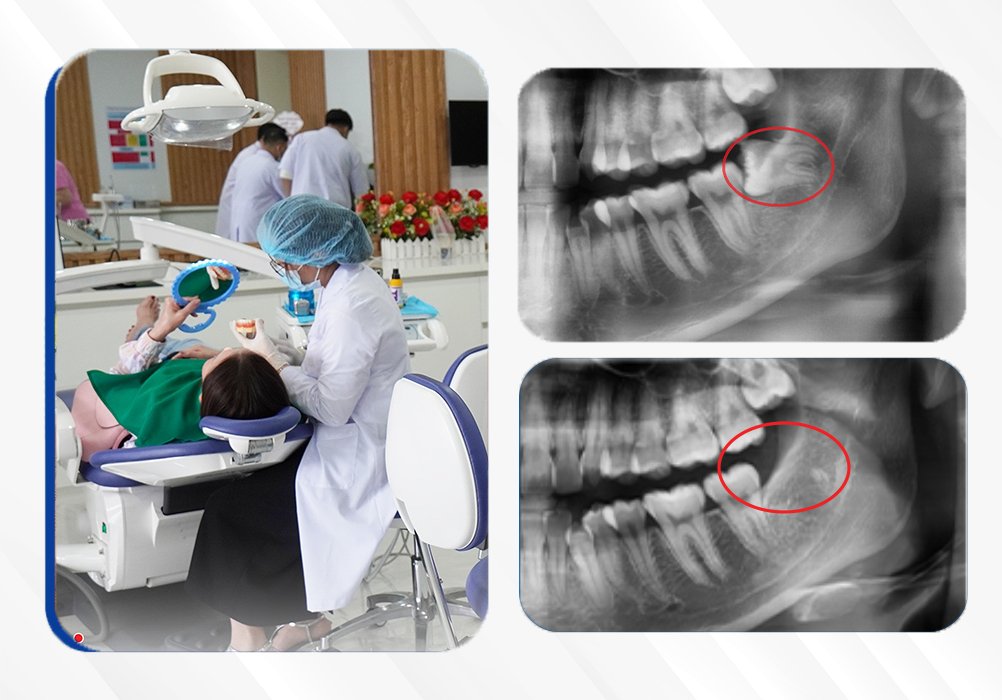

Nguyễn Thị Minh Tâm

Nhổ răng khôn mọc lệch